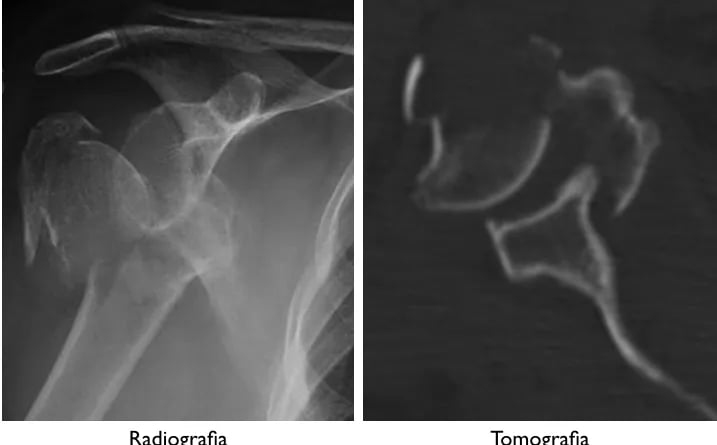

Fratura Proximal do Úmero

A fratura da extremidade proximal do úmero é uma das fraturas mais comuns. Ela ocorre mais frequentemente em idosos do sexo feminino, e está relacionada à osteoporose. Ocorre geralmente após quedas ao solo.